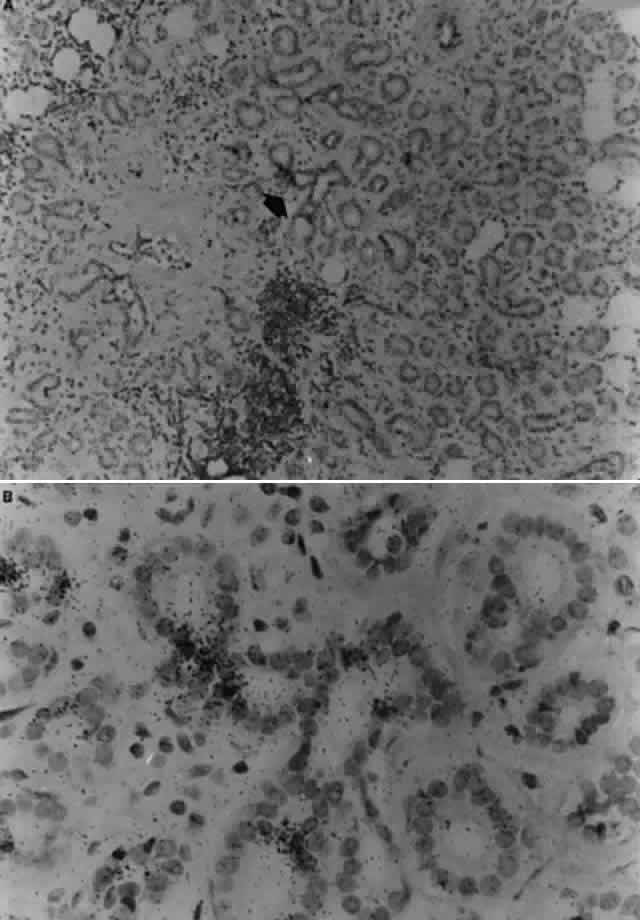

Recently, Palay and associates described a 21-month-old boy with bilateral, anterior stromal, nummular opacities which progressed in 1 month to confluent peripheral infiltrates associated with stromal vascularization.75 Paired acute and convalescent serum showed a greater than fourfold rise in antibody against EBV early antigen. Serologic tests for syphilis, HSV, and varicella-zoster virus were negative. Among the 12 reported cases of EBV interstitial keratitis, there appears to be three distinct morphologic patterns of the corneal lesions. Subepithelial infiltrates (type I) most closely resemble those of adenovirus epidemic keratoconjunctivitis. Anterior-to-midstromal opacities (type II) occur in two forms: small, granular, circular or ring-shaped opacities with minimal associated inflammation, or larger, blotchy, pleomorphic infiltrates with active inflammation. Full-thickness or deep stromal keratitis (type III) is pleomorphic and blotchy, predominantly involves the deep peripheral cornea, and may mimic luetic interstitial keratitis, or when unilateral, HSV stromal keratitis. -The clinical course in two of the reported cases suggests that one form of keratitis may progress toanother, and that deep or full-thickness peripheral infiltrates with vascularization may represent a later stage of the disease. One of the cases reported by Matoba and associates developed multifocal subepithelial opacities (type I) 1 month after acute IM.69 Eight months later, the now chronic keratitis had progressed to anterior stromal, pleomorphic, course, granular infiltrates (type II) which became confluent adjacent to the limbus (type III). Similarly, the young patient reported by Palay and associates75 demonstrated at initial presentation blotchy, anterior stromal, “nummular” infiltrates (type II), but 2 months later showed confluent peripheral opacities at all levels of the stroma (type III) associated with intrastromal vascularization. The pathogenesis of EBV-associated keratitis has not been established; however, the case reported by Pflugfelder and associates74 suggests that epithelial infection by EBV may lead to stromal keratitis. EBV was demonstrated in the dendrite by PCR and EBV-specific monoclonal antibody staining. The epithelial keratitis began 4 days after a chemical facial peel. The chemoexfoliant included phorbol ester, which can induce EBV replication in latently infected B lymphocytes and epithelia and has been implicated as a cofactor in the development of nasopharyngeal carcinoma. Pflugfelder and associates suggested that the keratitis was due to phorbol ester-induced reactivation of EBV latent within corneal epithelium. Although the detection of EBV genome in this case may be due to persistently infected cells in the corneal epithelium, the immunohistochemical evidence of EBV early antigen within the dendritic epithelium indicates a replicative EBV infection was occurring and implicates EBV as the cause of the keratitis. Interestingly, among the patients with EBV stromal keratitis described by Matoba and associates,69 two patients were noted to have punctate epithelial granularity adjacent to stromal opacities. It is unknown whether these epithelial changes occurred as a result of recent EBV replication within the corneal epithelium or were secondary to underlying stromal inflammation. EBV may infect the corneal epithelium and produce a dendritic epithelial keratitis without subsequent development of stromal keratitis. Wilhelmus reported a 16-year-old girl with heterophil antibody-positive IM who developed a unilateral follicular conjunctivitis and dendritic epithelial keratitis without stromal keratitis.68 EBV was cultured from conjunctival and tear specimens. Although the epithelial keratitis resembled that caused by HSV, no serum antibody to HSV types I or II was detected, nor could HSV be cultured from the ocular specimens. The examining physician later became ill with fever, vesicular glossitis, lymphopenia, splenomegaly, and heterophil antibody positivity suggesting possible transmission of EBV via the patient's tears. Tsai and associates recently reported the association of elevated EBV VCA antibodies in patients with iridocorneal endothelial (ICE) syndrome.76 Because lymphocytic infiltration of the endothelium has been observed histologically in corneal buttons obtained from patients with ICE syndrome,77 Tsai and co-workers postulated that the corneal endothelial disease in patients with the ICE syndromes may be due to EBV infection of the endothelium.76 However, at the present time, EBV has not been found in the endothelium of corneal buttons obtained at the time of corneal transplantation for ICE syndrome to confirm these serologic observations. SJ<auO>GREN'S SYNDROME Direct and indirect evidence has been reported that EBV plays a pathogenic role in the lacrimal gland pathology of primary Sjögren's syndrome. There are multiple case reports of primary Sjögren's syndrome developing immediately after serologically confirmed IM.78 In 1990, Pflugfelder and associates reported that primary Sjögren's syndrome patients have significant elevations of serum antibodies to EBV viral capsid and early antigens compared to patients with non- Sjögren's syndrome aqueous tear deficiency and normal controls.79 These results suggested that primary Sjögren's syndrome patients have chronic persistent EBV infection that is a risk factor for their disease. Subsequently, Pflugfelder and associates reported the results of studies evaluating peripheral blood mononuclear (PBMN) cells, lacrimal gland biopsies, and tear specimens from EBV-seropositive controls and primary Sjögren's syndrome for the presence of EBV genomes using PCR. EBV DNA sequences were amplified by PCR in 50% of Sjögren's syndrome PBMN cell specimens and 80% of the Sjögren's syndrome lacrimal gland and tear specimens.80 In contrast, EBV genomic sequences were detected in 32% of normal human lacrimal glands, but in none of the PBMN cell specimens from normal controls. Tsubota and collaborators reported the results of similar studies evaluating lacrimal and salivary gland biopsies from normal controls and primary Sjögren's syndrome patients for the presence of EBV genomes by PCR.81 They detected the presence of EBV genomes in 100% of lacrimal gland biopsies from Sjögren's syndrome patients, and in only 40% of lacrimal gland biopsies from normal controls. They also detected the presence of the EBV genome in the majority of salivary gland biopsies from Sjögren's syndrome patients; however, quantitative analysis of the number of EBV genomes indicated there was a 10-fold greater number of EBV genomes in lacrimal gland than in salivary gland biopsies from primary Sjögren's syndrome patients. Taken together, these studies indicate that EBV may persist in a small percentage of normal lacrimal glands, and that EBV genomes are found in the majority of lacrimal glands from primary Sjögren's syndrome patients, suggesting that EBV may be a risk factor for the pathogenesis of the lacrimal gland disease of Sjögren's syndrome. Reported studies using PCR to detect EBV genomes in normal and Sjögren's syndrome lacrimal gland biopsies did not indicate the infected cell types within the lacrimal gland, nor did they determine if the amplified EBV DNA sequences were from latent EBV genomes or replicating virus. The results of studies reported by Pflugfelder and associates82,83 suggest that EBV may persist in the normal human lacrimal gland in a latent nonpathologic state. The cellular site and state of genome expression in normal human lacrimal glands persistently infected with EBV appears to be similar to that reported to occur in normal salivary glands (Fig. 6).25 In contrast, the results of studies using in situ DNA hybridization and immunohistochemical techniques to evaluate Sjögren's syndrome lacrimal glands for EBV infection indicate that there may be a much more extensive infection of ductal epithelia than observed in normal lacrimal glands, as well as infection of mononuclear cells in areas of B-cell lymphoproliferation. EBV antigens were detected in both lymphocytes and epithelial cells in Sjögren's syndrome lacrimal glands; however, the pattern of antigen expression differs in these two cell types. EBV antigens associated with immortalization of B cells, LMP-1, and EBNA-2 were detected in mononuclear cells in areas of B-cell lymphoproliferation. B cells in Sjögren's syndrome lacrimal glands expressing EBV latent infection cycle antigens also expressed ICAM-1, CD-23 and CD-21, the typical repertoire of antigens upregulated by EBV following immortalization of B cells. Based on these findings, it appears that EBV infection of B lymphocytes in Sjögren's syndrome lacrimal glands may be responsible for the B-cell lymphoproliferation observed in these glands. In contrast, epithelial cells located in areas of lymphoproliferation in Sjögren's syndrome lacrimal gland strongly expressed early (EA-R) and late (VCA) EBV lytic-cycle antigens. These findings suggest that a lytic EBV infection may occur in epithelial cells in Sjögren's syndrome lacrimal glands. Because EBV genomes have been detected in the majority (80%) of tear specimens obtained from primary Sjögren's syndrome patients, it is possible that EBV-infected ductal epithelium may be the source of the virus shed into the tears. Similar to other EBV-associated neoplasias, a lymphoepithelial pathology is frequently observed in Sjögren's syndrome lacrimal gland biopsies.83 The lymphoepithelial pathology in Sjögren's syndrome lacrimal glands differs from nasopharyngeal carcinoma in that lymphoproliferation surrounding epithelium in Sjögren's syndrome lacrimal glands consists predominantly of B lymphocytes, whereas T cells typically surround epithelia in nasopharyngeal carcinoma.84 In lacrimal gland lobules with mild inflammation occurring in patients with Sjögren's syndrome, the B-cell lymphoproliferation is observed surrounding ducts in the center of the lobule and normal-appearing acini may still be present in the peripheral lobule. In more severely affected glands, the lymphoproliferation replaces all secretory acini and the ducts in areas of B-cell lymphoproliferation have an abnormal morphology and pattern of cytokeratin expression.83 PCR genotype analysis indicates that the majority of EBV-positive Sjögren's syndrome lacrimal glands are infected with type I EBV. Type I EBV strains efficiently transform B lymphocytes into continuous cell lines and the detection of this strain of virus in Sjögren's syndrome lacrimal gland is consistent with the B-cell lymphoproliferation observed in these lacrimal glands. This contrasts with normal lacrimal glands from which Type I EBV strains were not detected; these glands were infected exclusively by EBV strains with EBNA-2 deletions typical of nontransforming Type II EBV. Although the sample size in these studies is small, and additional studies are needed to confirm our results, the difference in virus strain between normal and Sjögren's syndrome lacrimal glands may be important in the pathogenesis of the lacrimal gland destruction in Sjögren's syndrome. The predominant EBV-specific CTLs in humans are human leukocyte antigen (HLA) Class I restricted (CD8) T cells.85 EBV-specific CTLs have been reported to efficiently lyse HLA-restricted B cells infected with type I strains and poorly recognize cells infected with Type II EBV strains.86,87 CD8 T cells are the predominant population surrounding acini and proximal ducts in normal lacrimal glands.88 One potential role of CD8 cells in the lacrimal gland may be to recognize and destroy cells within the lacrimal gland infected with type I EBV. These cells could include EBV-infected ductal epithelium or B cells which continuously traffic into the gland. Lacrimal gland cells infected with type II EBV strains may be able to elude recognition by resident CD8 CTLs. This hypothesis may explain the fact that only EBNA-2 deleted type II EBV DNA was found in normal lacrimal glands. The higher frequency of EBV infection in the blood and lacrimal glands of Sjögren's syndrome patients may result from the inability of CTLs from Sjögren's syndrome patients to recognize and destroy cells infected with certain strains of type I EBV. Misko and associates studied paternal EBV-specific CTL activity against EBV-infected lymphoblastoid cell lines established by infecting peripheral blood B cells obtained from five different children in a family with either the B95-8 or the BL 74 EBV strains.89 The parental HLA type was A1, 11; B51, 8; DR3, 7. Parental EBV-specific CTLs lysed haploidentical EBV cell lines infected with the B95-8 strain expressing the HLA A11, B51, DR7 paternal haplotype, but failed to lyse haploidentical cell lines infected with the B95-8 strain expressing the HLA A1, B8, DR3 paternal haplotype. Cell lines expressing either of the paternal HLA haplotypes infected with the BL74 strains were efficiently lysed by paternal CTLs. The authors found that failure to lyse HLA B8-restricted cell lines infected with the B95-8 strain was not due to T-cell dysfunction, and they concluded that the failure to lyse was probably due to an inability of the HLA B8 antigen to present the immunodominant B95-8 epitope to HLA Class I restricted CTLs. B95-8 cell lines coated with the BL74 immunodominant peptide were efficiently lysed by paternal CTLs. Interestingly, the HLA B8, DR3, DW52A, DQW2 haplotype is strongly associated with primary Sjögren's syndrome (relative risk of 8).90 As suggested by Misko and associates, the HLA B8 haplotype association in Sjögren's syndrome patients may be one of the principal risk factors for their abnormal EBV infection.89 Alternatively, the EBV-induced lacrimal gland B-cell lymphoproliferation in Sjögren's syndrome may be related to other cellular immune derangements previously reported to occur in Sjögren's syndrome patients with severe dry eyes. |